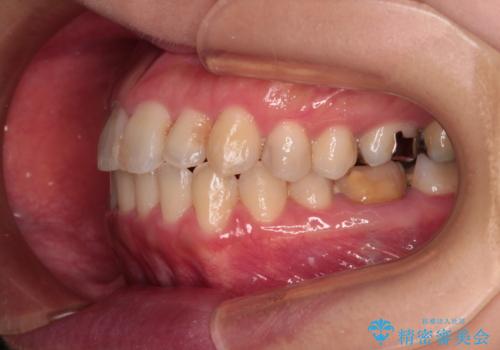

- 前歯の捻れを気にして来院された患者様です。

上顎前歯が捻れて前方に飛び出しており、下顎前歯もそれに沿うようにデコボコとなっていました。

IPR(歯と歯の間を削る処置)によりスペースを獲得して上下前歯のデコボコを改善し、インビザラインにて矯正治療を行うこととしました。